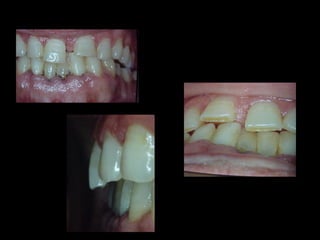

Mi casuística

Antes (arriba) Después (derecha)

La paciente fue manejada iatrogénicamente por 5 años

Utilizando diferentes implementos ortodóncicos

La regla es clara: Laterognatias de más de 2º son quirúrgicas